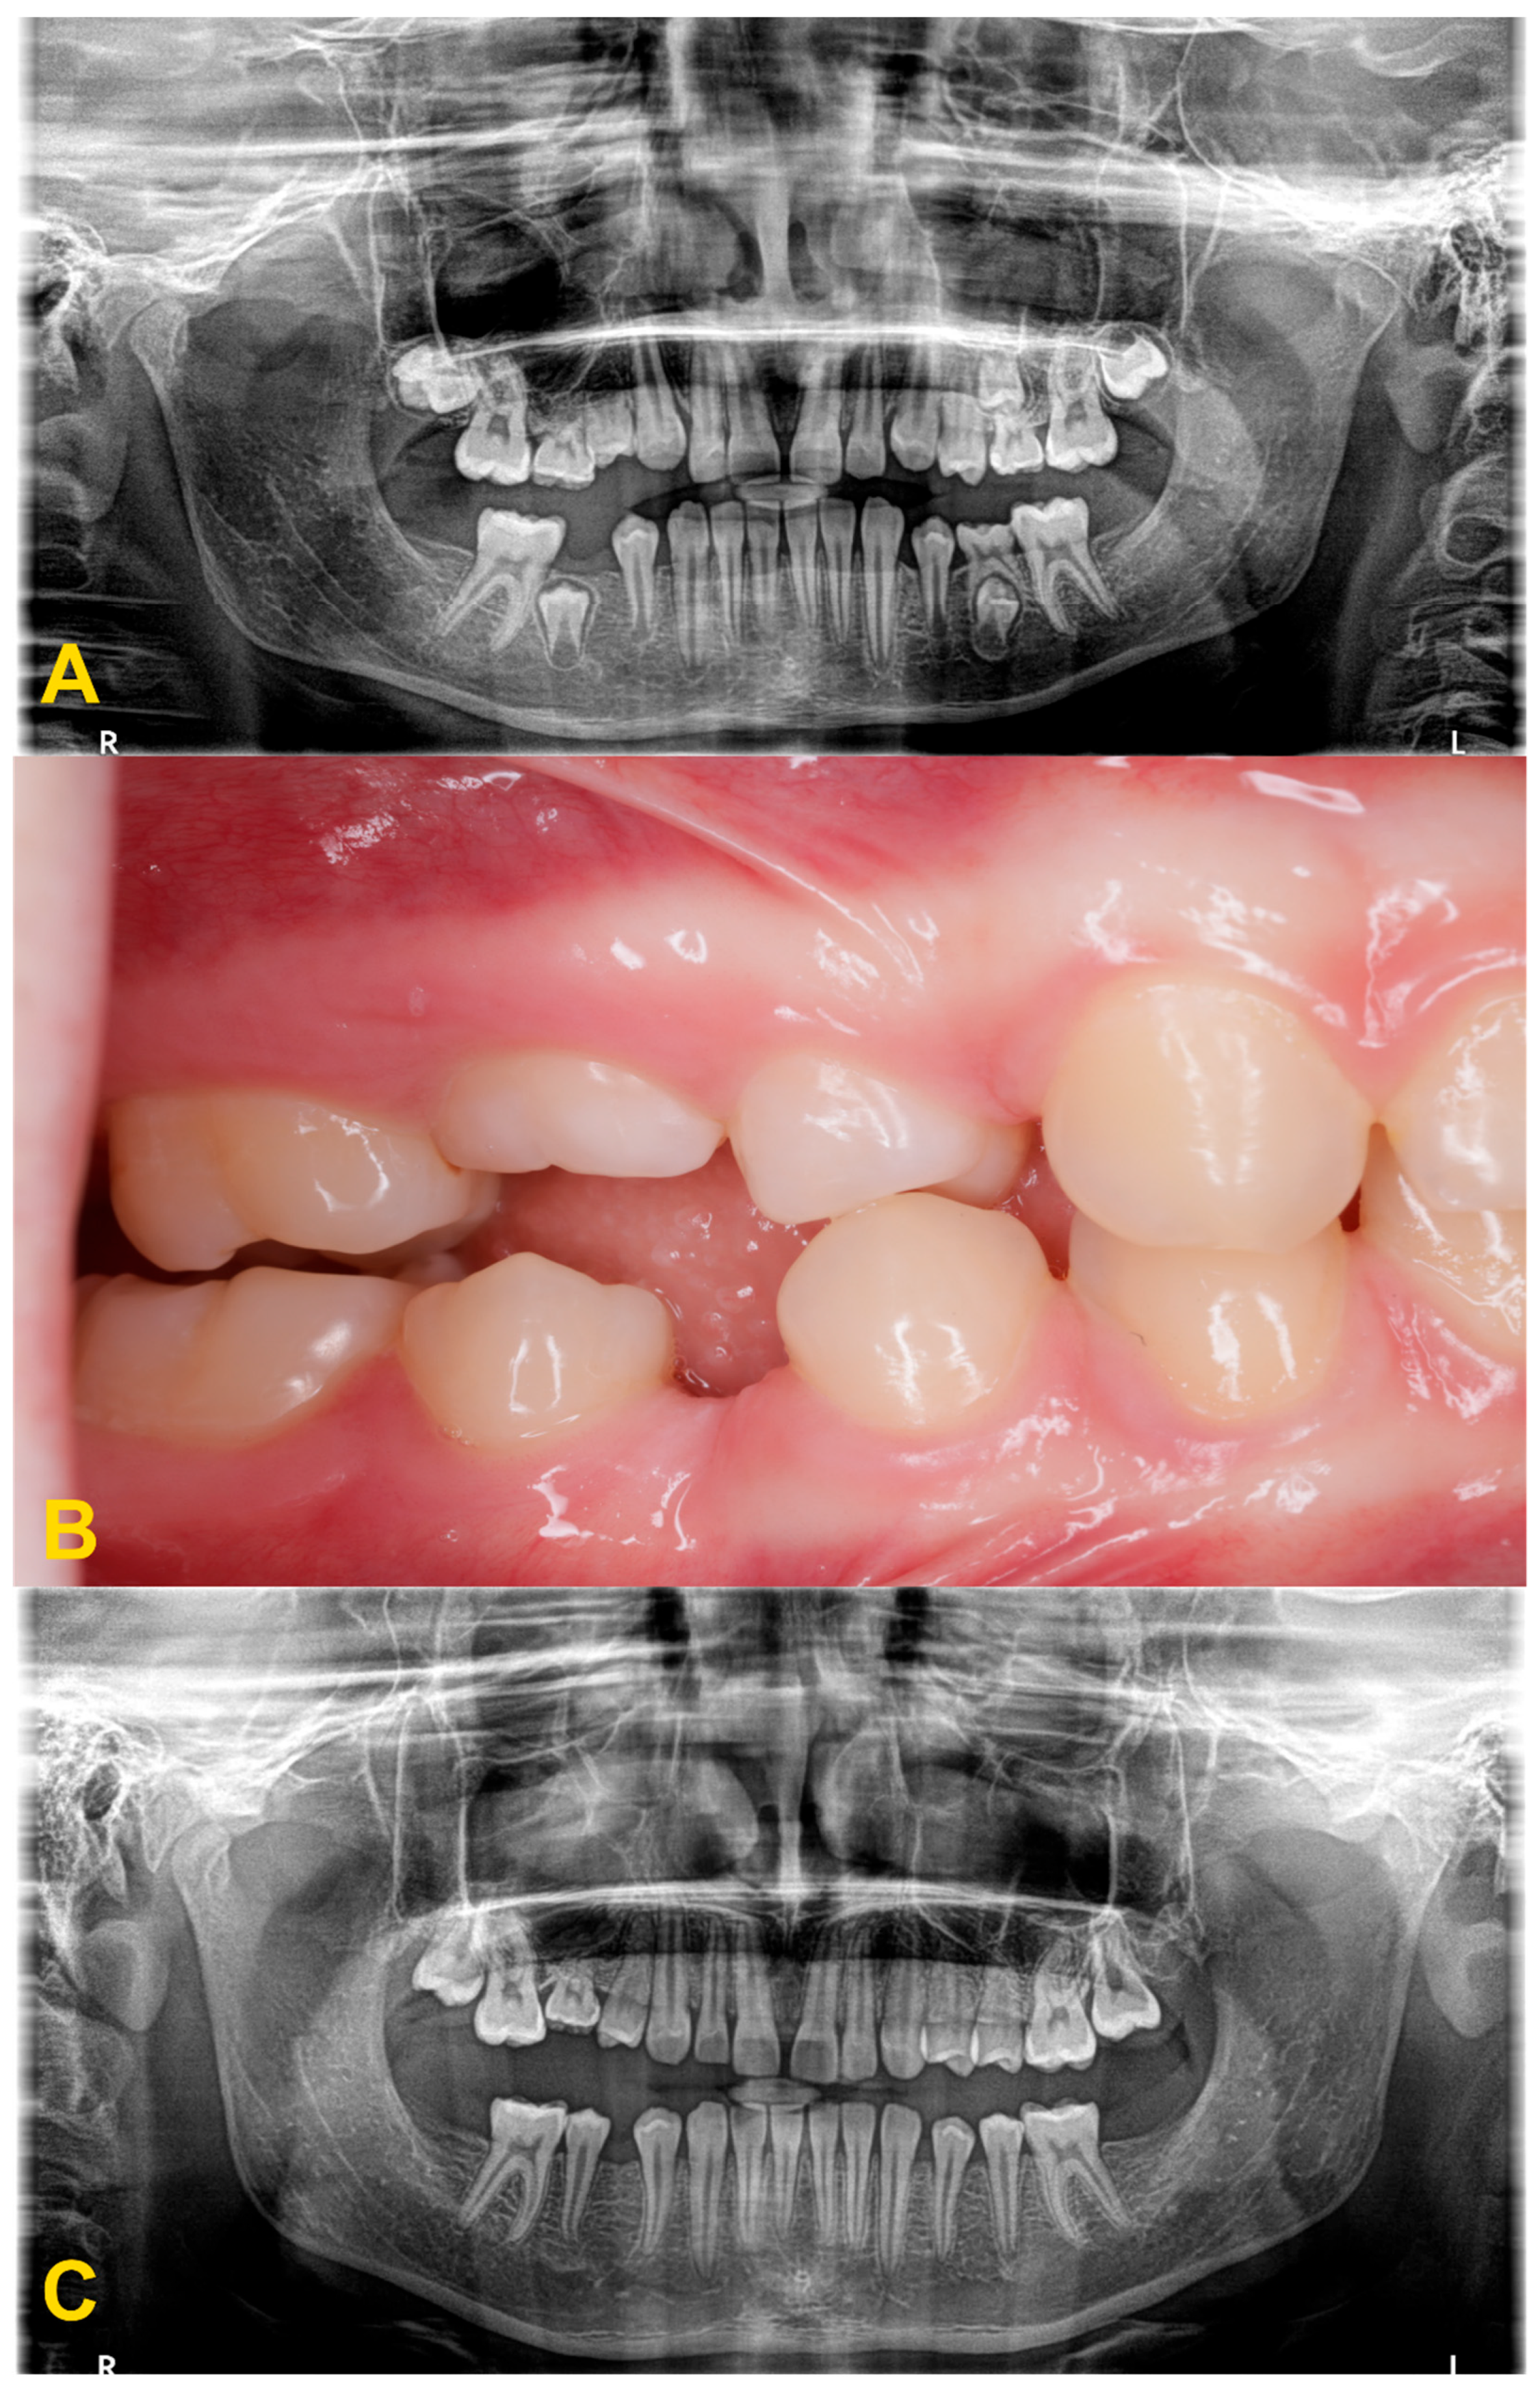

2. Diagnostics and Treatment